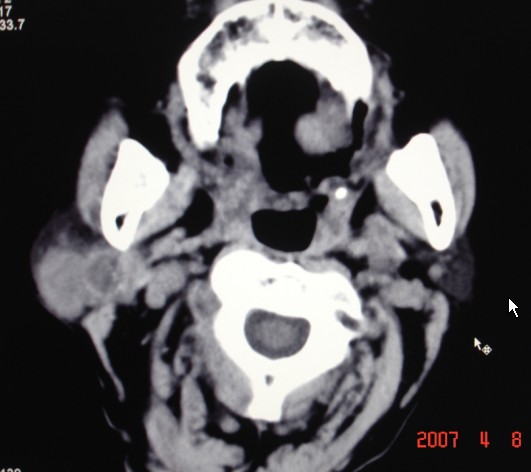

以下是引用zjzjr在2007-4-9 13:27:00的发言:[br]右侧腮腺深浅叶可见一混杂密度区,含有实性及囊性成.考虑右侧腮腺混合瘤,建议ct增强扫描。

以下是引用jiangjing在2007-4-9 15:09:00的发言:[br]考虑右侧腮腺肿瘤[混合瘤可能性大],其他待排[br]建议ct增强扫描。